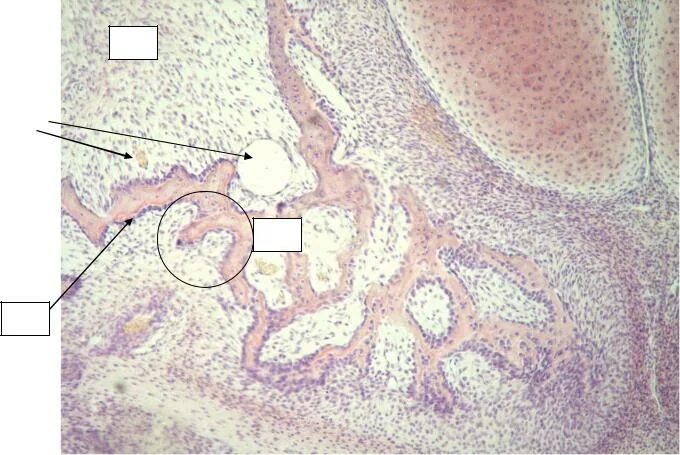

Гистология челюстей